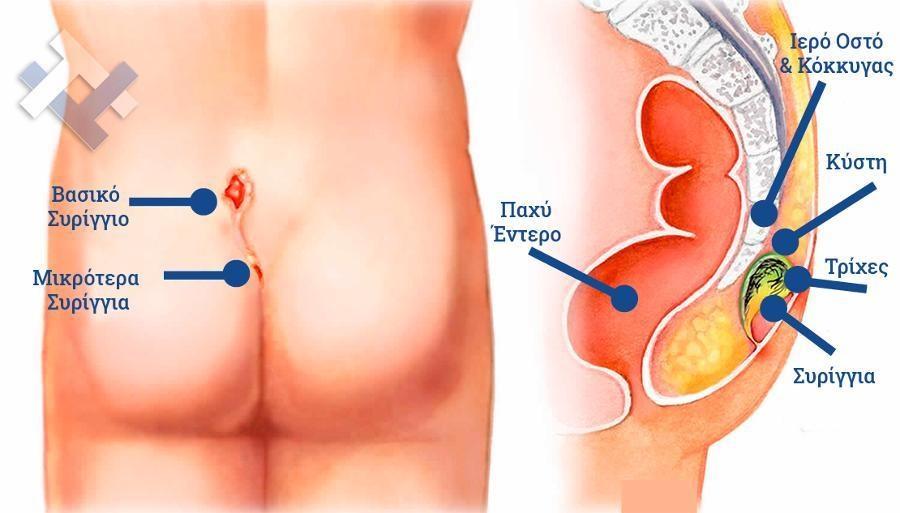

Ο Γενικός Χειρουργός Λιάγκος Γεώργιος MD PhD εκτελεί τις επεμβάσεις Λαπαροσκοπικά, Ενδοσκοπικά, Ανοιχτά Ελάχιστα Επεμβατικά και με Laser. Η θεραπεία εξατομικεύεται σε κάθε ασθενή ανάλογα με τις ανάγκες του. Αναλαμβάνει περιπτώσεις όπως κήλες και κοιλιοκήλες (αντιμετώπιση βουβωνοκήλης, αντιμετώπιση ομφαλοκήλης, θεραπεία επιγαστρικής κήλης, κήλη των αθλητών (Σύνδρομο κοιλιακών προσαγωγών), αντιμετώπιση μετεγχειρητικής κήλης, θεραπεία Μηροκήλης), πέτρες στη χοληδόχο κύστη, λαπαροσκοπική χολοκυστεκτομή, αντιμετώπιση Κύστη Κόκκυγος με λέιζερ (laser), παθήσεις πρωκτού, χειρουργική laser σύγχρονων κυκλικών ινών (αιμορροΐδες αντιμετώπιση, θεραπεία αιμορροϊδων με laser (LHP), αφαίρεση αιμορροΐδων με υπερήχους (HALL-RAR), χωρίς Χειρουργείο με ελαστικούς δακτυλίους (Τεχνική BARON-RBL), θεραπεία ραγάδας πρωκτού (Ραγάδα δακτυλίου), θεραπεία περιεδρικού συριγγίου, θεραπεία περιεδρικού αποστήματος, κονδυλώματα πρωκτού Θεραπεία, δερματικό ράκος (Skin tag) εκτομή, αντιμετώπιση Kνησμού, καρκίνος πρωκτού θεραπεία), παθήσεις Δέρματος, χειρουργική με laser CO2, αφαίρεση μορφωμάτων δέρματος - βιοψίες, αφαίρεση ελιάς (Σπίλου), σμηγματογόνος κύστης θεραπεία, αφαίρεση λιπώματος, είσφρυση όνυχος χειρουργείο, καρκίνος δέρματος θεραπεία, οξεία σκωληκοειδίτιδα, παθήσεις Λεπτού και Παχέος Εντέρου, ειλεός λεπτού εντέρου, εκκολπωμάτωση (Εκκολπωματίτιδα) σιγμοειδούς, καρκίνος παχέος εντέου, κολοστομίες, port χημειοθεραπείας κ.α. εξυπηρετώντας Παγκράτι και γύρω περιοχές.